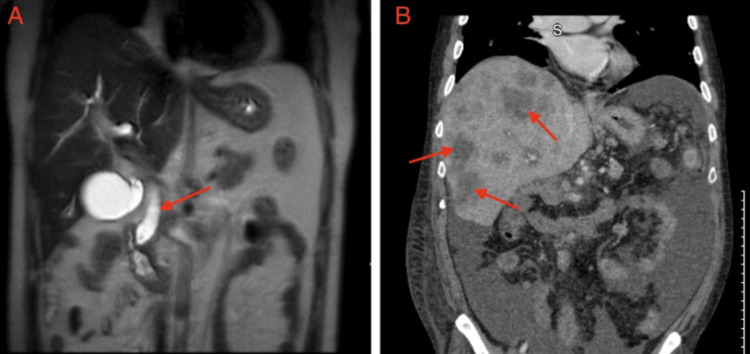

A 40-year-old male with a history of alcohol use for more than 20 years presented to the emergency department with painless jaundice and dizziness for two weeks associated with occasional loose bowel movements. On arrival, his blood pressure was 144/86 mmHg, heart rate was 95 beats per minute, respiratory rate was 18 breaths/min, and temperature was 99.2°F. Physical examination was notable for upper abdominal tenderness, severe jaundice, and icterus. Laboratory tests were notable for a hemoglobin of 6.3 g/dL, as well as elevated alanine aminotransaminase and aspartate aminotransaminase (160 and 153 U/L, respectively), elevated alkaline phosphatase (513 U/L) and elevated total bilirubin (9.5 mg/dL), as shown in Table 1 along with other pertinent admission labs. He was subsequently transfused with 2 units of packed red blood cells with an appropriate response. General surgery was consulted to rule out acute cholecystitis, which did not recommend any surgical intervention. Magnetic resonance cholangiopancreatography (MRCP) showed small choledocholithiasis in the distal CBD, CBD dilatation, and no signs of acute cholangitis (Figure 1A). He was eventually transferred to another facility for endoscopic retrograde cholangiopancreatography (ERCP) and endoscopic ultrasound, which revealed a 24 mm x 14 mm ampulla mass and a dilated CBD with biopsy showing moderately differentiated adenocarcinoma without microsatellite instability. An ERCP was attempted but was unsuccessful due to the inability to visualize the ampulla for cannulation. Interventional radiology (IR) was then consulted for a percutaneous transhepatic cholangiogram and drain placement. Pre-procedure magnetic resonance imaging (MRI) showed a 1.9 x 1.4 cm periampullary mass and pancreatic tail lesion demonstrating rim enhancement, adding further suspicion for a solid pancreatic neoplasm. The patient underwent an exploratory laparotomy and pancreaticoduodenectomy, otherwise known as the Whipple procedure, one month after initial presentation. While the pathology of the pancreas tail lesion was benign, the periampullary mass pathology demonstrated a periampullary adenocarcinoma characterized as stage III (T3bN2M0) moderately differentiated intestinal type with lymphovascular invasion (LVI), 3 cm in size with 0.9-cm invasion into the pancreas. The pathology report further characterized the neoplasm as positive for both LVI and perineural invasion (PNI) and also found four out of nine lymph nodes to be positive for carcinoma. The patient followed up with oncology a month after surgery, where he was referred for a Mediport placement and radiation oncology evaluation.

The case was discussed in a tumor board meeting to determine the best course of treatment, and the team agreed to use chemotherapy followed by chemoradiation as an adjunctive treatment. The patient was started on leucovorin calcium (folinic acid), fluorouracil, irinotecan hydrochloride, and oxaliplatin (FOLFIRINOX), but was lost to follow-up after completing two cycles. He was admitted 18 months later for a pulmonary embolism and was discharged on apixaban. CT of the abdomen and pelvis at that time showed multiple liver lesions and sub-centimeter nodules in the lungs concerning metastasis (Figure 1B). The patient was admitted a month later for severe abdominal pain and underwent an EGD for melena and hematemesis, which revealed a non-bleeding anastomotic ulcer and erythematous gastric mucosa. Liver biopsy showed metastatic pancreatic adenocarcinoma. Oncology was re-consulted, and the patient agreed to palliative chemotherapy and received seven cycles of FOLFIRINOX before being lost to follow-up.